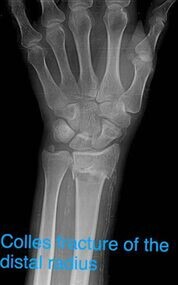

I wrote this article after going through the experience of fracturing my distal radius. I wanted to bring all the tools and information together that I used to return to a fully functioning arm, to benefit others going through this tricky time.